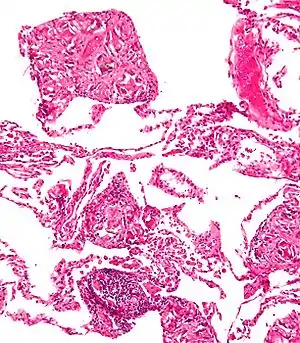

Foreign body giant cell reaction to nylon suture material

Foreign body granuloma